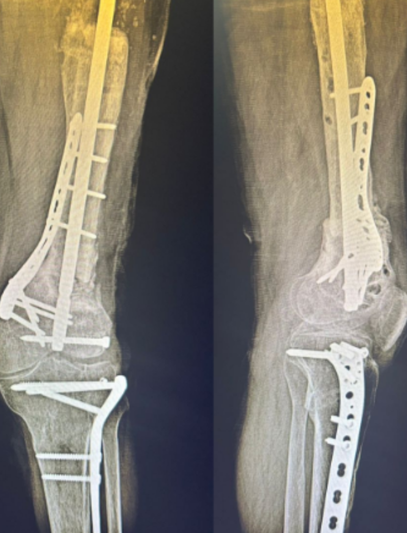

Tras un accidente de tránsito, Yessenia presentó una fractura expuesta con un defecto óseo de 10 cm en su pierna. Había recibido tratamientos previos sin éxito y su movilidad estaba en riesgo.

Con la técnica de osteogénesis por distracción y el uso de un tutor circular Ilizarov, se inició un proceso de regeneración ósea progresiva, acompañado de un seguimiento cercano.

Hoy Yessenia evoluciona favorablemente, conserva movilidad en su rodilla y tobillo, y está recuperando la independencia que pensaba perdida.